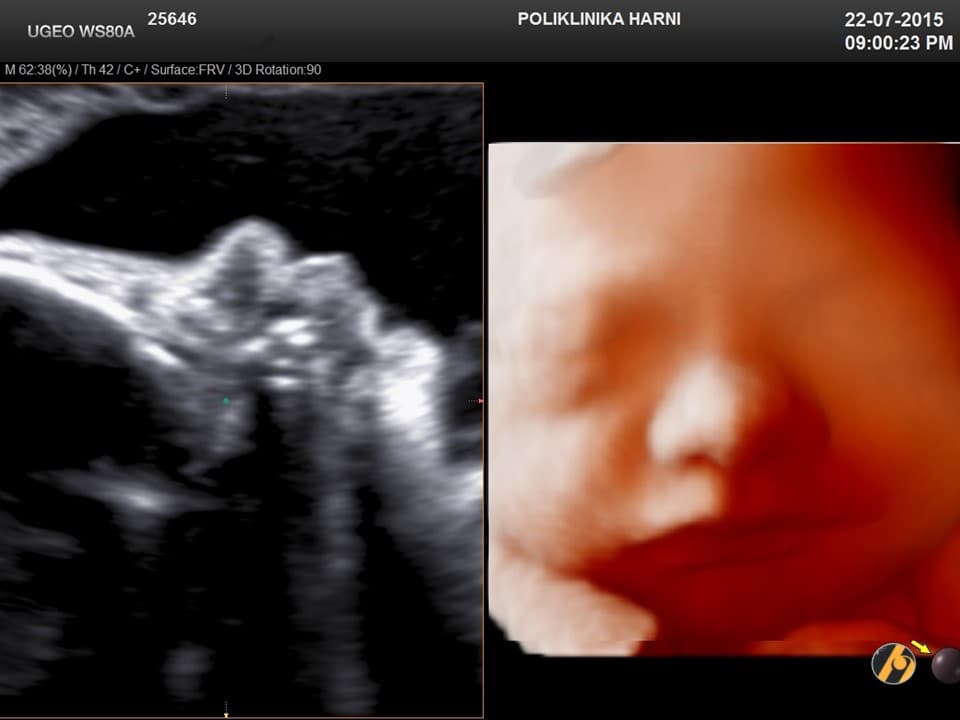

Vaša beba intenzivno napreduje, prije svega povećava se njena težina, u ovo vrijeme dobiva gotovo 200 - 250 g/tjedan. Zadebljava se potkožno masno tkivo i beba zadobiva konačni bucmasti izgled. U ovom tjednu nokti dosežu vrhove prstiju, a kod nekih beba mogu biti i duži, te se nakon porođaja mogu naći čak i ogrebotine na licu koje potječu iz intrauterinog života.

Vaša beba dugačka je oko 44 cm, a teška 2,300 – 2,550 g.

beba